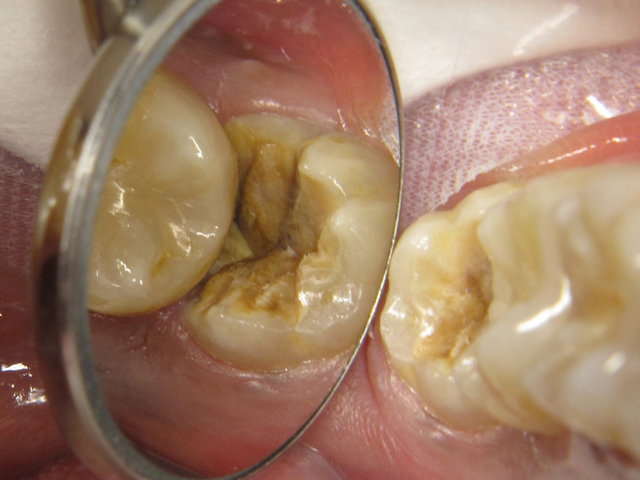

Tiefe Karies wegen eines benachbarten Weisheitszahnes

Tiefe Karies wegen eines benachbarten Weisheitszahnes ...

Composit-Füllung by CLINICDENT ✓